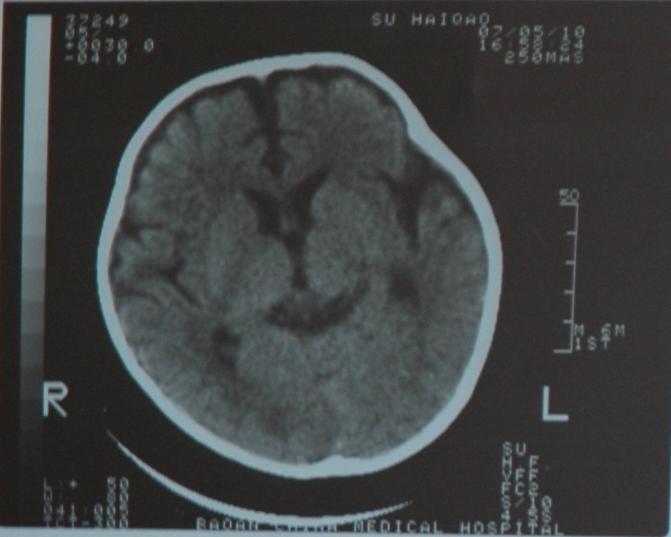

检查部位:头颅ct扫描

层厚:10mm     层距:10mm

扫描所见:双侧额颞部颅骨内板下方见对称性带状脑脊液样低密度影,并向前纵裂延伸,两侧大脑半球、脑干及小脑实质密度未见异常,侧脑室及三脑室略宽,双侧额叶脑沟深深加宽。四脑室形态无变形、移位或扩张,中线结构居中。

ct诊断:1、外部性脑积水(少量)。2、侧脑室、三脑室略宽,双侧额叶脑沟增深加宽,请结合临床。